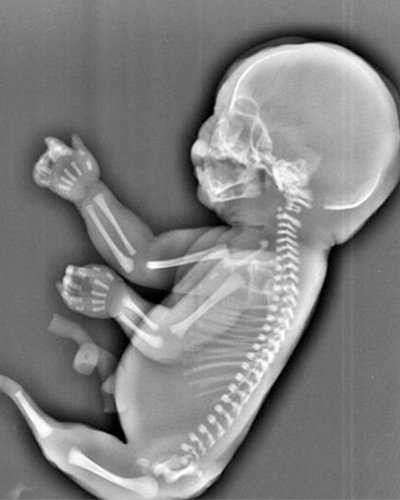

Theo đó, thay vì phát triển như những đứa trẻ bình thường khác, hai chân của thai nhi 6 tháng tuổi này lại dính liền với nhau trông không khác là bao so với đuôi của người cá.

Hình ảnh siêu âm cũng cho thấy thai nhi không có bàng quang và hai lá gan phát triển không đồng đều.

Các bác sĩ ở thành phố Nghi Xương, Trung Quốc cho rằng thai nhi trong bụng của cô Wu mắc 'hội chứng người cá'.

Đây là hội chứng rất hiểm gặp với tỷ lệ mắc bệnh rất nhỏ, chỉ 1/100.000 thai nhi và nguyên nhân gây ra căn bệnh này cho đến nay vẫn là một bí ẩn trong y học.